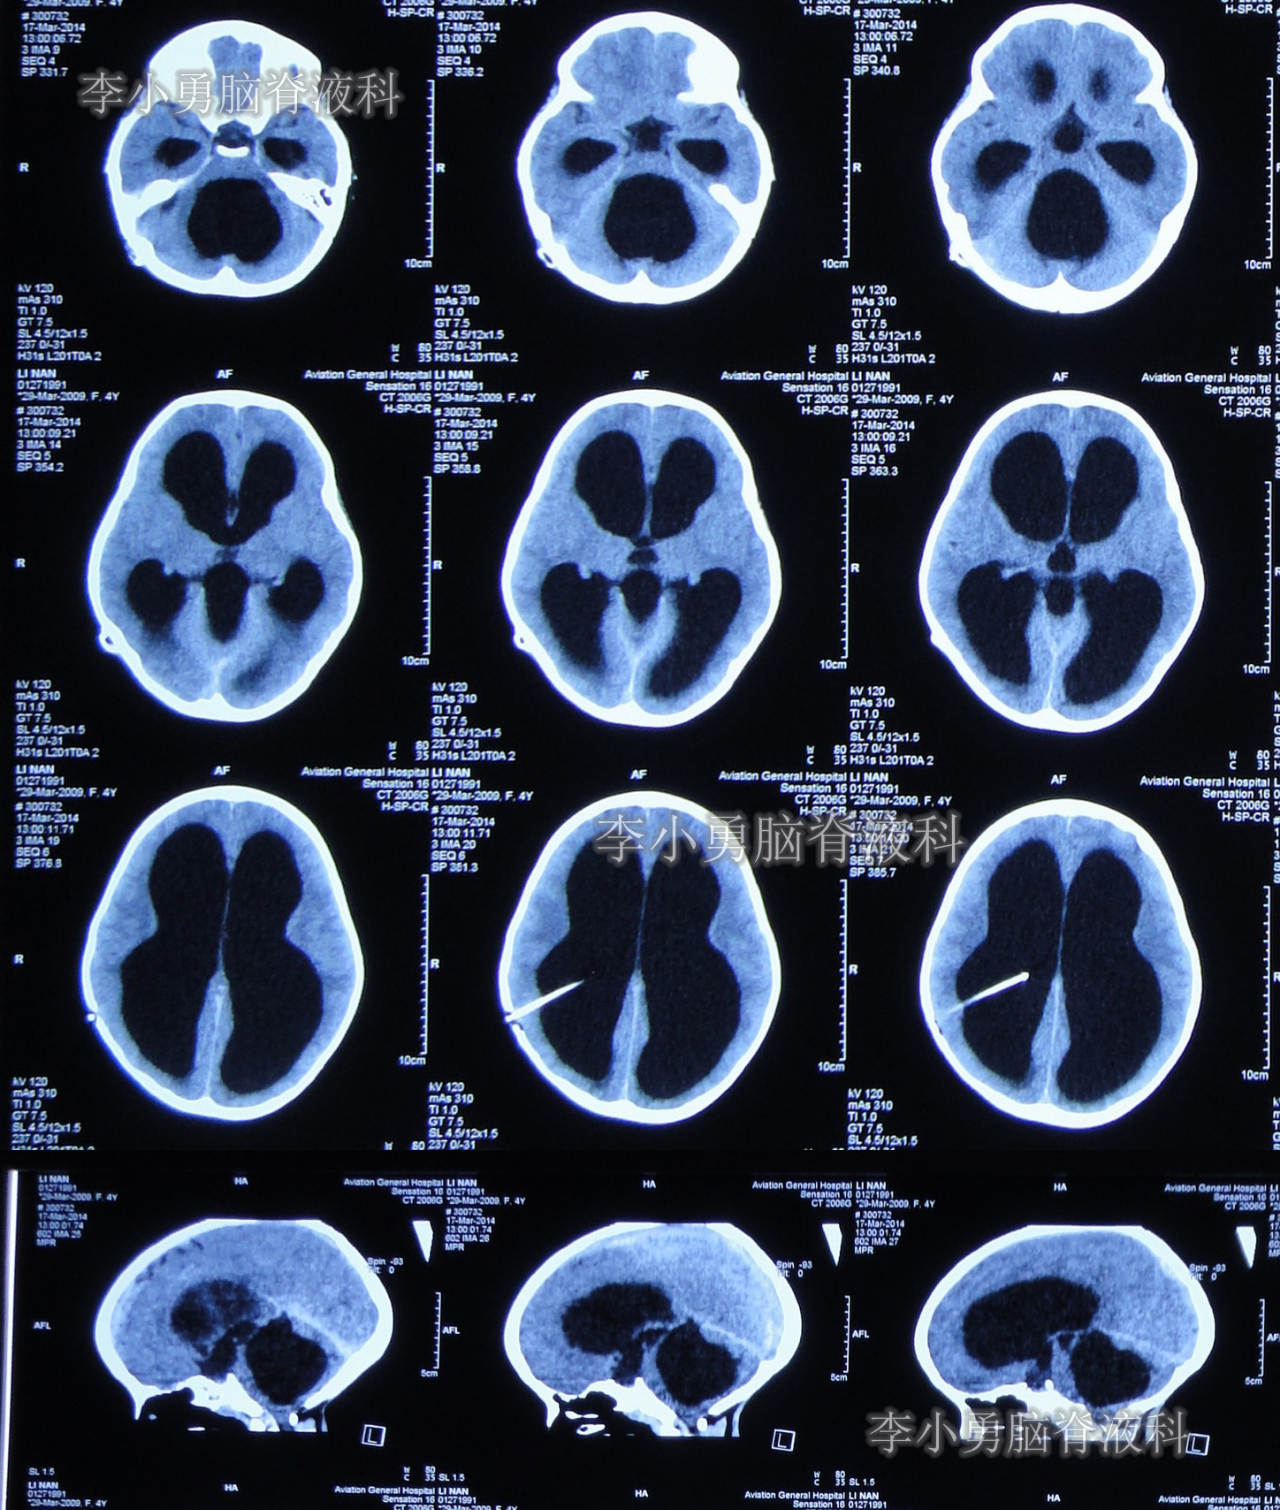

于2014年2月11日即脑室心房分流术后第122天时,患儿突然再次出现头痛和呕吐的症状,立即又第3次返回河南省郑州市某三甲医院神经外科住院治疗,当天查头颅CT显示脑室系统再度扩张严重(图-2)。

图-2:2014年2月11日头颅CT

第3次住院后第10天即2014年2月21日,复查头颅CT显示脑室系统仍扩张严重(图-3)。

图-3:2014年2月21日头颅CT

当天头颅CT示第四脑室及脑室系统又有明显扩张(图-16);CT检查后,床旁急行左额角脑室外引流术。

图-16:2014年5月6日头颅CT

脑室外引流术后第2天即2014年5月7日,复查头颅CT示脑室系统仍扩张,分流管脑室端游走脱位(图-18)。

图-18:2014年5月7日头颅CT

脑室外引流术后第3天即2014年5月8日,接受了脑室腹腔分流脑室端调整术;术后当日查头颅CT示脑室系统扩张减轻(图-19)。

图-19:2014年5月8日头颅CT